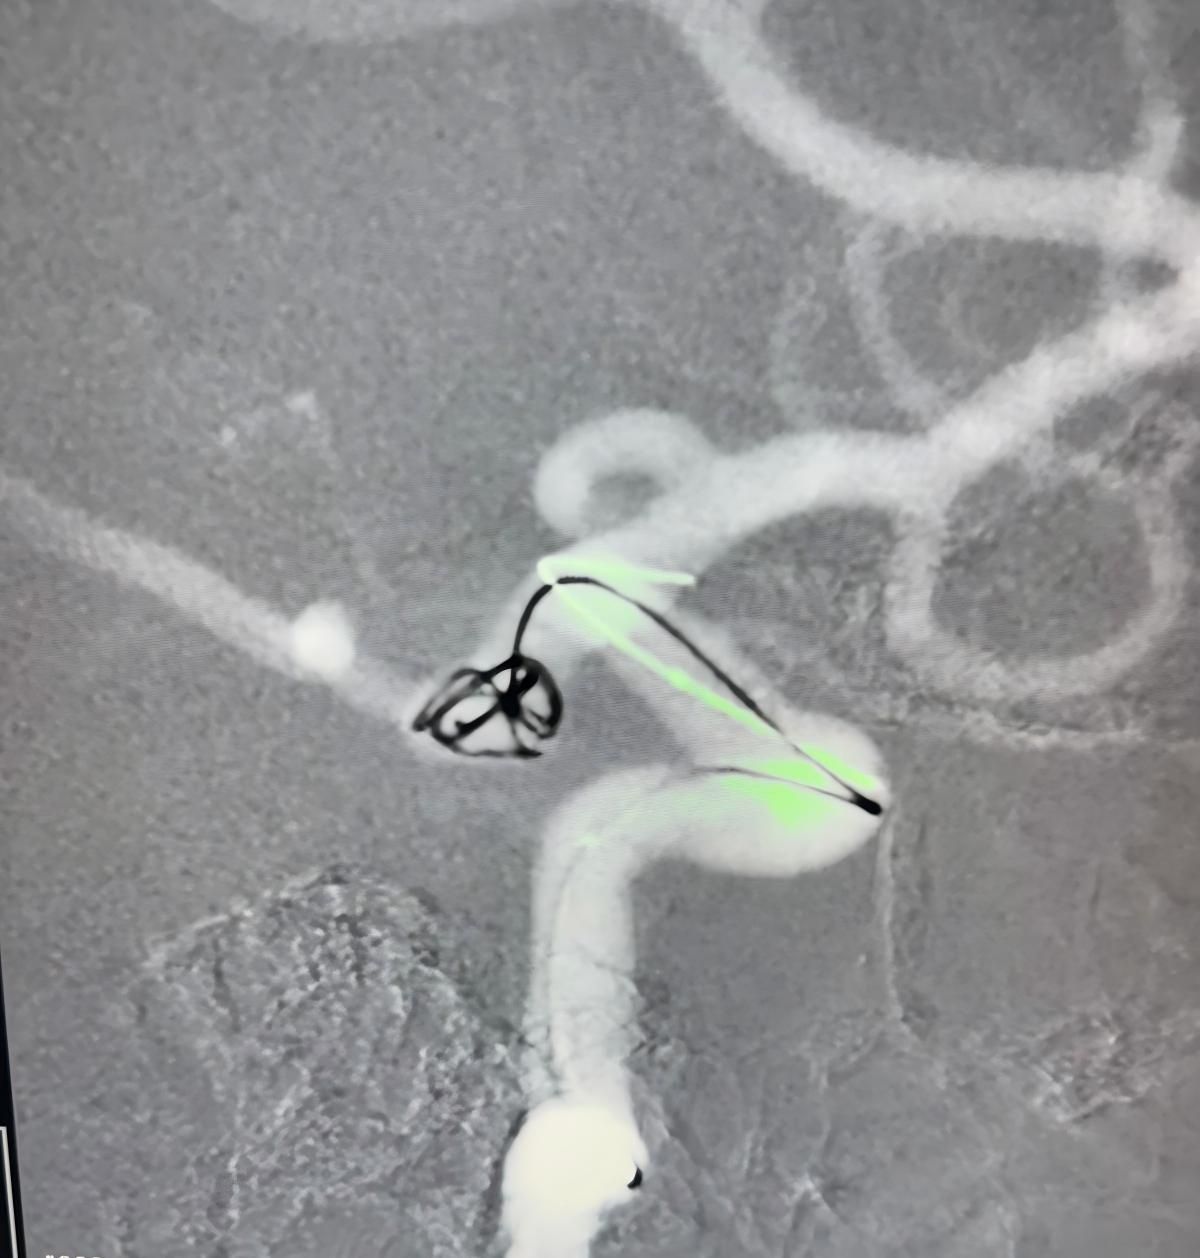

Лечение использовалось Нува®Отвод потока (TJED-D 5,0-14), перденсатор®3D катушка и Frepass®Микрокатетер (TJMC18 Plus) для аневризмы задней сообщающихся артерий.

Доктор Мутис подчеркнул отличную видимость устройства и отметил, что извлечение было гладким. Он выразил большое удовлетворение в связи с окончательным результатом.